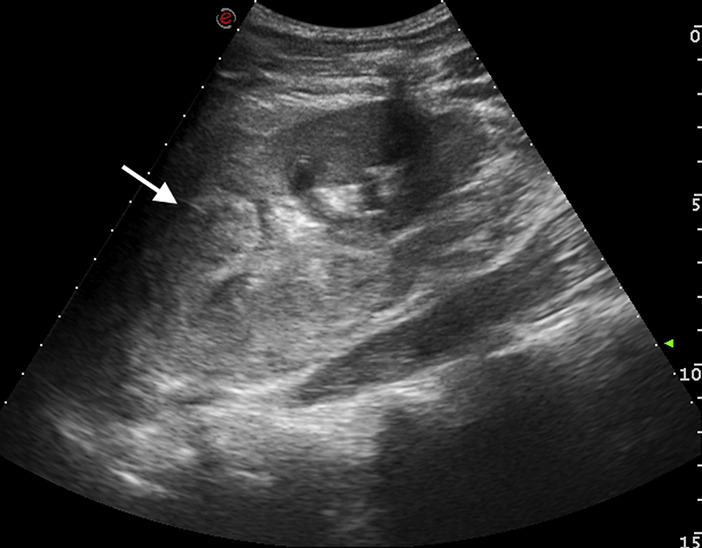

- A 15-year-old previously healthy boy was admitted for a blunt abdominal trauma owing to a cycling crash. On admission he was alert; blood pressure and pulse rate were 145/95 mm Hg and 75 beats/min, respectively. Physical examination result was remarkable for severe left-sided flank pain with guarding. No others injuries were found. His urine was like blood and laboratory tests showed a normal hemoglobin level, at 13.5 g/dL, with hematocrit level 40.9%.

- An abdominal ultrasonographic scan showed major left kidney trauma (Figure 1). A computed tomographic (CT) scan confirmed a grade IV renal laceration, according to the American Association for the Surgery of Trauma classification (Figure 2).